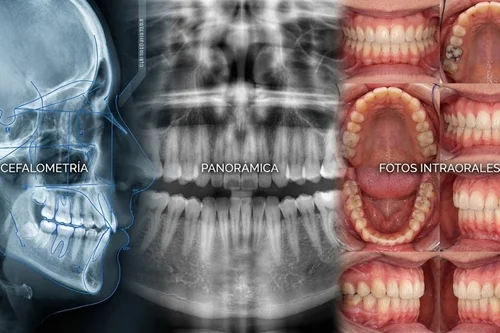

Paquetes de Ortodoncia Full

Carpetas digitales completas. Incluye radiografías, fotos clínicas y trazados cefalométricos listos para el inicio de tratamiento.